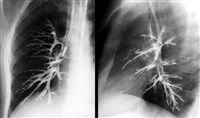

Бронхография — метод рентгенологического исследования трахеи и бронхов после введения в них рентгеноконтрастного вещества. В обычных условиях при рентгенологическом исследовании бронхи и трахея остаются невидимыми. Для получения при рентгеноскопии или рентгенографии теневого изображения трахеи и бронхов в дыхательные пути (после их обезболивания) вводят контрастные вещества (йодированные растительные масла, водорастворимые контрастные вещества, суспензии контрастных веществ в масле и водной среде). С помощью бронхографии диагностируют заболевания легких, бронхов и трахеи (опухоли, бронхостеноз). Бронхография противопоказана при общем тяжелом состоянии, сердечно-сосудистой декомпенсации, заболеваниях почек, повышенной чувствительности к йоду. Впервые бронхография была произведена человеку в 1918 году американским врачом Ш. Джексоном. В России первая бронхография была выполнена в 1923 году.